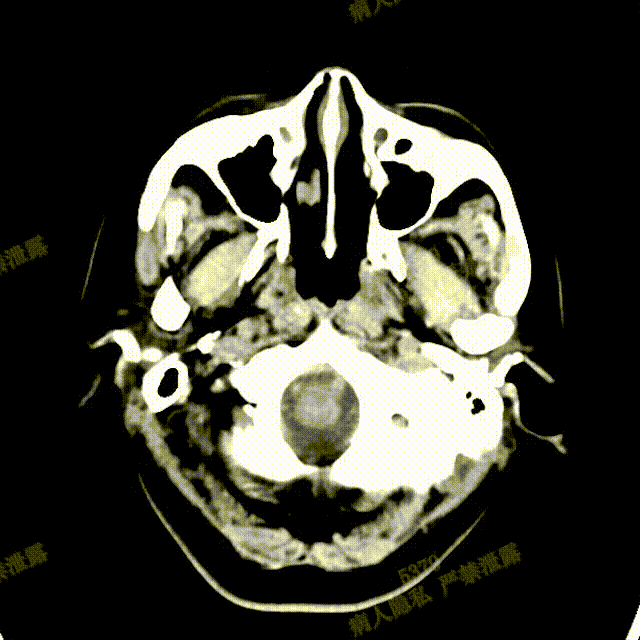

术中DSA造影:右侧颈内动脉工作角度及3D造影,显示右侧颈内动脉海绵窦段动脉瘤。

术中DSA造影:左侧颈总动脉3D造影及左侧椎动脉正位造影。

完全释放FRED 5514血流导向密网支架,正、侧位造影及术后CT复查结果观察,载瘤动脉通畅、支架贴壁良好、动脉瘤内造影剂滞留、颅内未见明显异常。